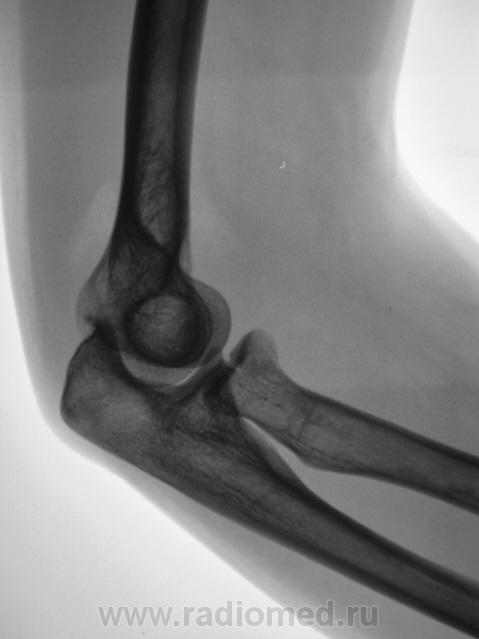

Боковая проекция.

Предположу продольный перелом головки луча с допустимым смещением.

Хочется услышать мнение коллег по поводу "жировых подушечек". Как они, среагировали или нет?